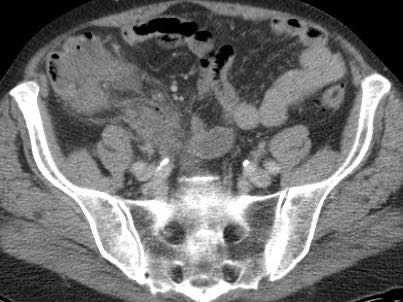

Ở bệnh nhân này với đau hố chậu phải kéo dài 18 giờ, CT chỉ cho thấy hình ảnh thâm nhiễm mỡ tối thiểu xung quanh ruột thừa 8,5 mm (mũi tên).

Siêu âm với kỹ thuật ép có kiểm soát đã cho thấy rõ ràng mô mỡ viêm tăng âm, không thể ép xẹp (đầu mũi tên) xung quanh ruột thừa.